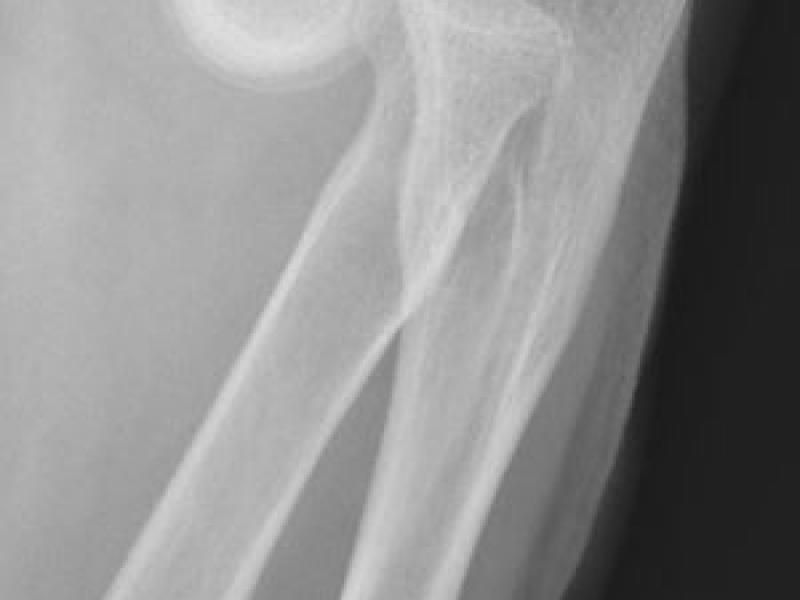

What's the Diagnosis? By Dr. Sandhya Ashokkumar

December 16 2020

A 68 yo F presents to the ED s/p fall. She slipped walking